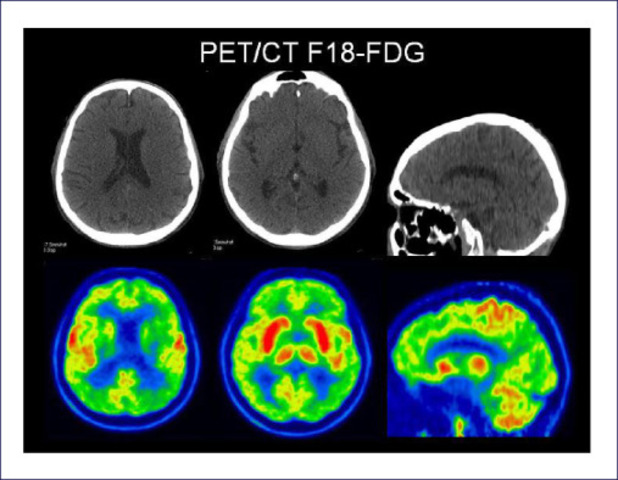

• Resonancia magnética funcional (FMRI) y  la tomografía por emisión de positrones (PET)

Resonancia magnética funcional (FMRI) y la tomografía por emisión de positrones (PET)

Permitido visualizar la actividad cerebral durante la realización de diferentes tareas cognoscitivas (por ejemplo, hablar, leer, pensar en palabras, etc.) surge un nuevo modelo en la interpretación de la organización cerebral de la cognición, el denominado “modelo funcional”, uso creciente de procedimientos estandarizados de evaluación: la Escala de Memoria de Wechsler, la Prueba de Boston para el Diagnóstico de las Afasias, la Prueba de Clasificación de Wisconsin, entre otras.